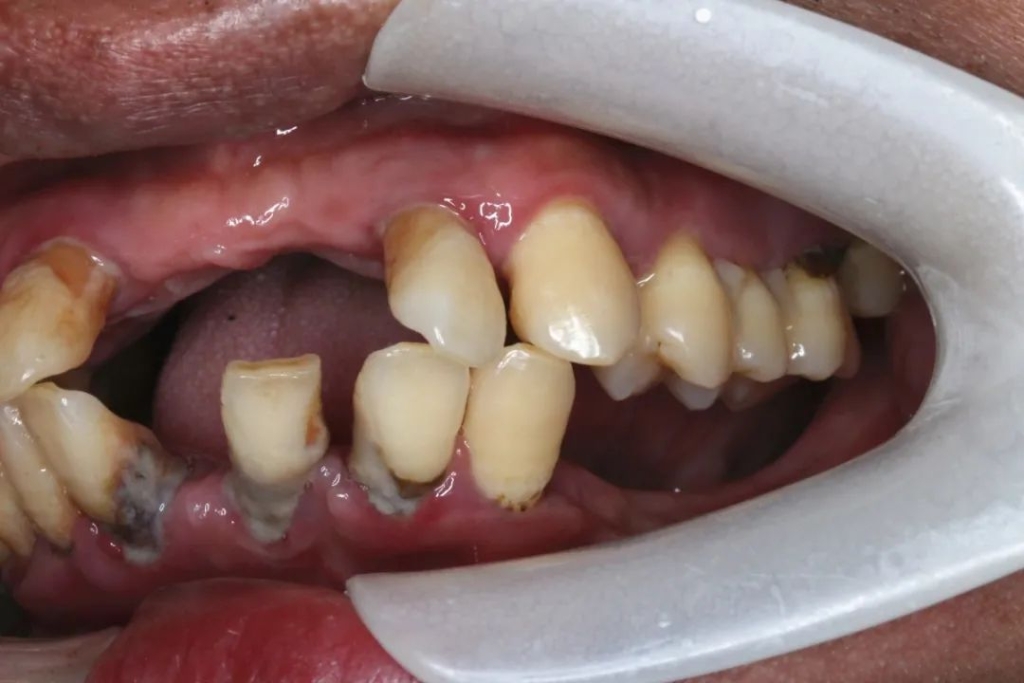

陈先生今年37岁,年纪轻轻就已经是一位资深“老烟杆”,每天几乎要抽掉一包烟,而且他还不常刷牙,即便刷牙,也只是马虎一下漱漱口,有时候刷出血他也不当回事。久而久之,他的牙发出了“抗议”:牙龈萎缩,牙根外露,牙齿松动。

口腔科王超君医生对他的牙齿进行了全面检查,结果让所有人都大吃一惊。陈先生的牙周病非常严重,导致原本与牙槽骨长在一起的牙根都浮了起来,只在牙肉里浅浅地埋着,导致整口牙都松动了。“陈先生来的时候身上一股烟味,吸烟对牙齿的损伤不是只有烟滞的问题,对牙根细胞的破坏更加大,再加上刷牙习惯不好,牙齿就容易出问题。”说起陈先生,王超君仍印象深刻。

图片来源于网络▲